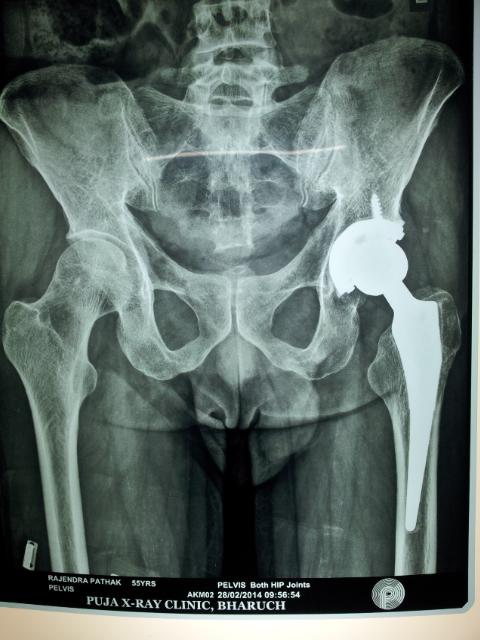

Traumatic arthritis is a type of arthritis resulting after few years of a hip fracture that has been treated. It requires removal of nail, pin etc and introduction of a new artificial hip joint THR

X-rays are used to determine the extent of degeneration to the cartilage or bone and may suggest a cause for the degeneration of the hip joint.